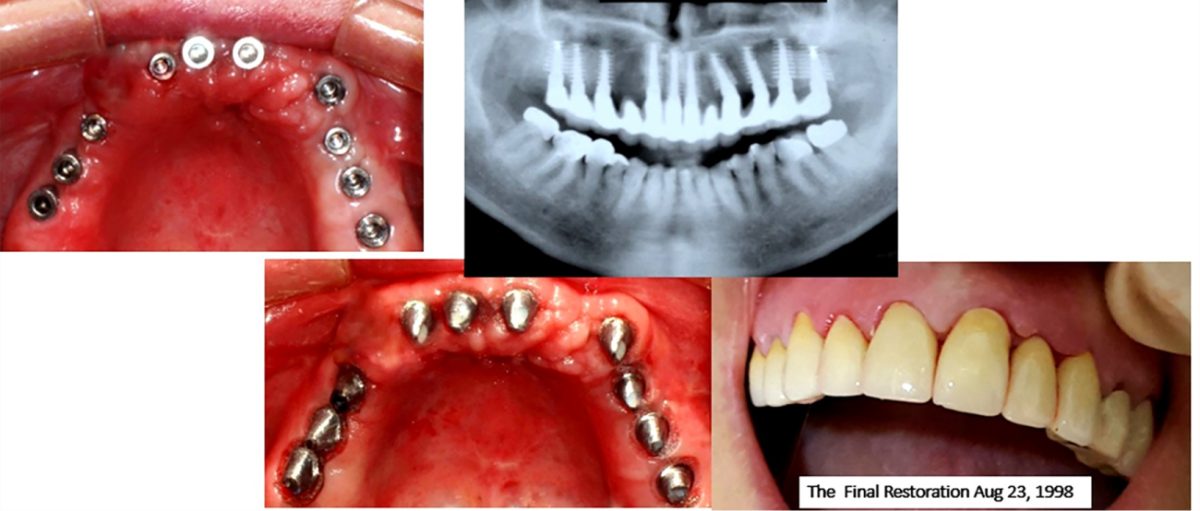

The Immediate Load implants are essentially Non-submerged, require only single-stage surgery, and are loaded with a provisional or final restoration.

- To obtain full-arch rehabilitation a min. of 6-8-10 implants are adequate, to achieve a predictable outcome.

- The splitting of implants reduces the stresses on the interfaces & enhances the stability, retention, and predictability of implants. The Splinting is attained by using a titanium bar of Ø1.0-1.5 mm, which is welded [19] labiolingually to all the placed implants, close to the gingiva utilizing the intraoral titanium welder [20], and is left in place for 3-4 months’ time. This splinting technique drastically reduces the risk of implant failure during chewing and helps in eliminating or minimizing the damage done by translation or lateral forces thereby evenly distributing the load and lessening the stress over immediately placed fixtures.

Conclusion: The osseo-manipulation technique stands at the forefront of implant dentistry, representing a transformative leap towards predictable outcomes and heightened patient satisfaction. By meticulously preserving bone and soft tissue integrity, minimizing surgical trauma, and enabling immediate loading, this technique addresses the escalating demand for efficient and aesthetically pleasing implant solutions. Throughout our study, we utilized a diverse array of implants and systems featuring varying diameters, lengths, shapes, and surface characteristics. Incorporating both immediate provisionalization and loading strategies, we achieved an impressive average survival rate nearing 95%. Compared to traditional bone grafting methods and surgical guides, osseo-manipulation demonstrates superior prognosis and outcomes. It fosters the development of stable bone quality, supporting natural implant positions with harmonious emergence profiles. This approach ensures consistent aesthetics, reduces complication risks by eliminating foreign grafts, and significantly shortens treatment times, thereby lowering overall costs for patients.